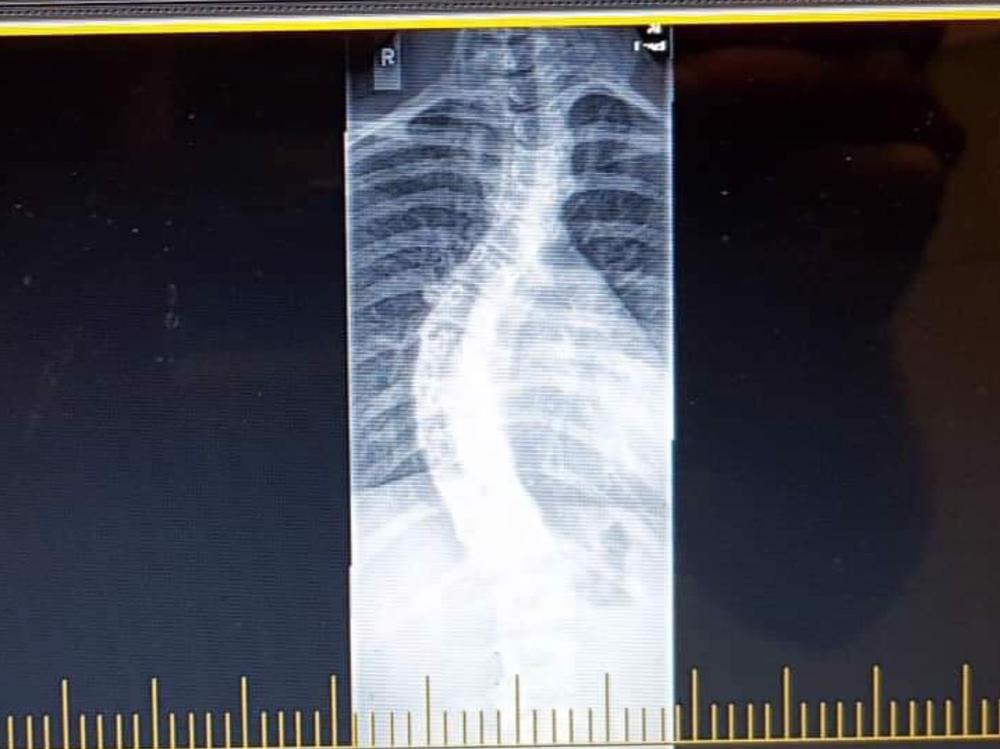

In October I had my surgery. It was a long lead up as we had to drive down to Dunedin Hospital. My surgery ended up taking 9 hours. During my surgery I had an endoscopic release and posterior fusion. My beginning degree was 71degrees but I came out of surgery 13degress. I am now fused from T2-L1 with 2 metal rods and many screws.